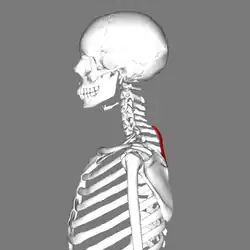

Le muscle petit rhomboïde est un muscle pair du dos reliant l'épaule au rachis.

Le muscle petit rhomboïde forme la partie supérieure du muscle rhomboïde et est situé sous le muscle trapèze.

Le muscle petit rhomboïde nait des processus épineux de la septième vertèbre cervicale et de la première vertèbre thoracique, ainsi que du bas du ligament de la nuque.

Le muscle petit rhomboïde se dirige obliquement en bas et latéralement.

Le muscle petit rhomboïde se termine sur le bord médial de la scapula, au niveau de la racine de l'épine scapulaire (au-dessus du muscle grand rhomboïde).